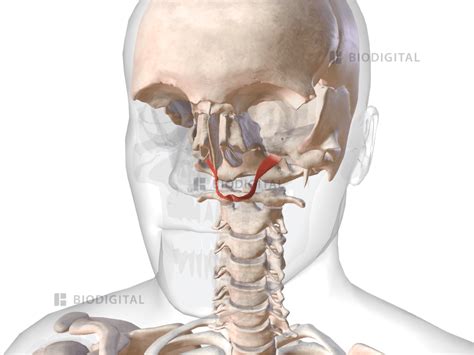

Levator Veli Palatini

Discover the anatomy and function of the Levator Veli Palatini muscle. Learn how this crucial palatal muscle controls velopharyngeal closure, aids in soft palate elevation, and regulates eustachian tube function during swallowing and speech. Explore its role in oral physiology and clinical implications for speech disorders in this comprehensive guide to understanding velar movement and muscle mechanics.